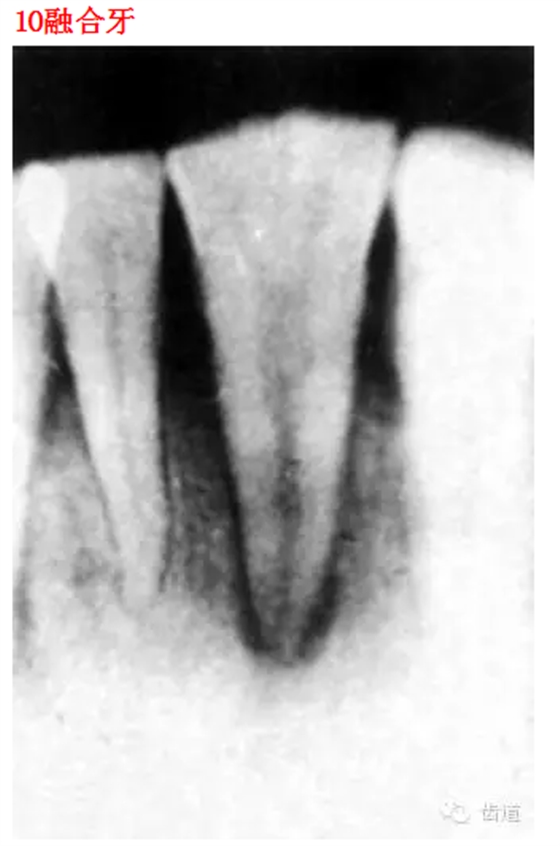

26種口腔病變X光片